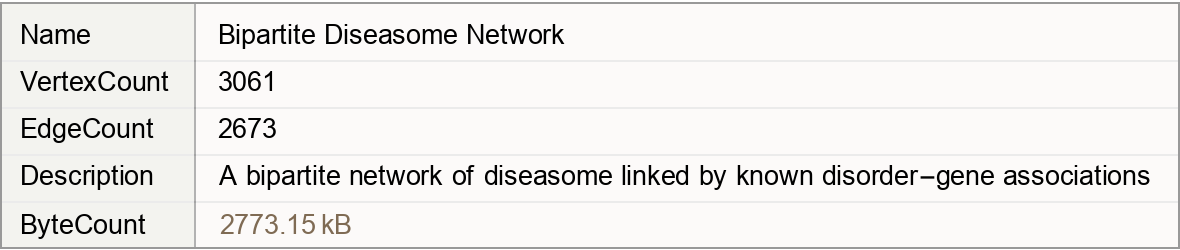

A bipartite network of diseasome linked by known disorder-gene associations

A network of disorders and genes linked by known disorder-gene associations, indicating the common genetic origin of many diseases. Genes associated with similar disorders show both higher likelihood of physical interactions between their products and higher expression profiling similarity, supporting the existence of distinct disease-specific functional modules. Annotation values contain "Type" and "ID".

(3061 vertices, 2673 edges)